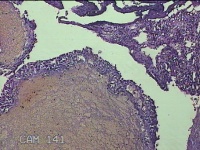

左侧卵巢黄体

性别

女

年龄

34岁

临床诊断

左侧卵巢黄体破裂

一般病史

下腹疼痛11小时。

标本名称

大体所见

灰白暗红色囊壁样组织3x2.3x0.3cm一堆,表面光滑,内壁高低不平,切面灰白暗红色,囊壁厚约0.1cm。

有可能,所提供图片不具有诊断价值。